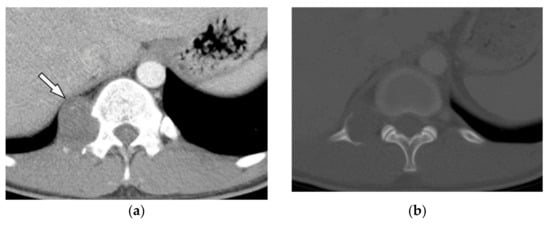

On multidetector CT scan, lipomas are homogenous and have similar attenuation to macroscopic fat with approximate −100 HU radiodensity (Figure 23); other non-adipose components such as calcification and septa might also be seen. On MR imaging, signal intensity is identical to subcutaneous fat on T1-weighted and T2-weighted images. It typically does not enhance gadolinium-enhanced MR images except for septa with less than 2 mm thickness [8,16,50,51].

Figure 23.

A 34-year-old man, with a case of SVC thrombosis with incidental finding. (a) Non-contrast-enhanced CT in axial plane demonstrates well-circumscribed lesion in the right posteromedial aspect of the chest wall with similar attenuation to subcutaneous fat with no internal septa. Multiple collaterals are also shown in the anterior aspect of the chest wall, maybe formed due to underlying SVC occlusion. (b) Axial plane CT of another patient shows large posteromedial chest wall mass with attenuation similar to adjacent subcutaneous fat compatible with lipoma.